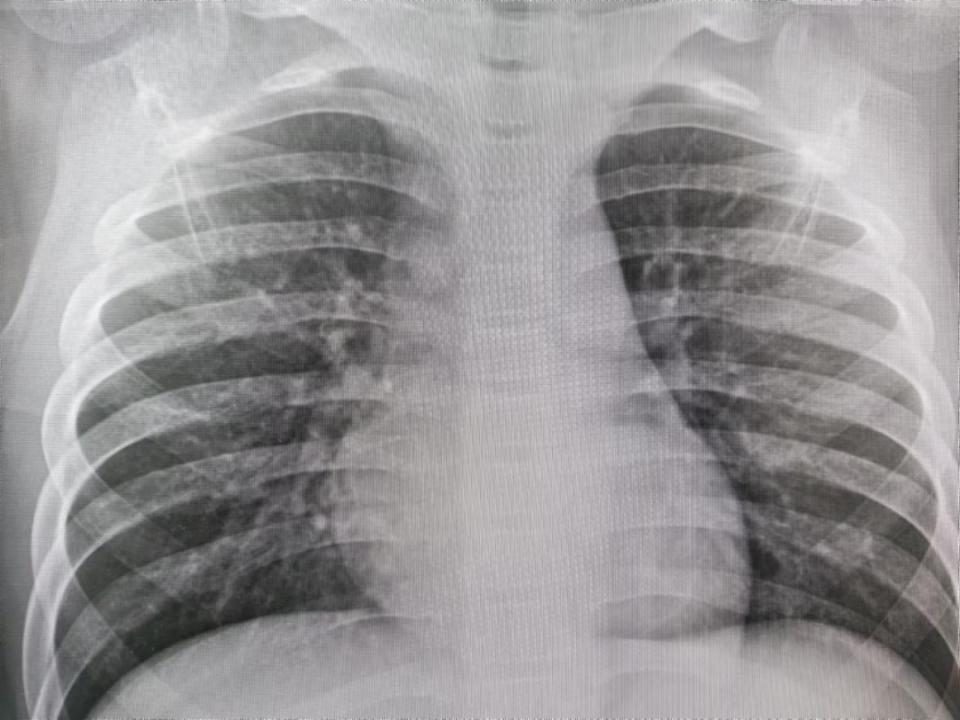

肺炎胸片儿童

大家来看看这张小孩子 的胸片

儿童肺炎时胸片怎么看呢